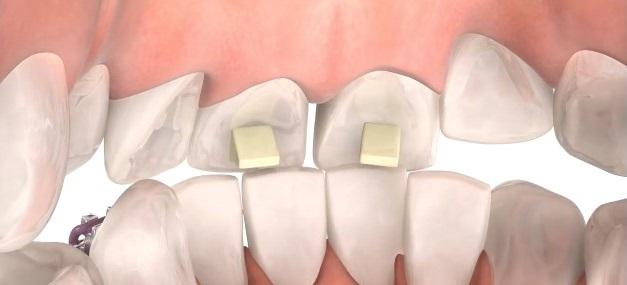

Bite turbos are small platforms placed on the inside of the upper front teeth, to prevent full closure of the teeth. When upper and lower braces are placed at the same time, the top teeth bite down and contact the lower braces. These are placed when a person has a very deep bite where if bite turbos where not placed they would be able to bite the lower brackets off.